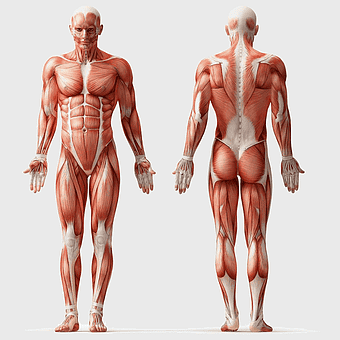

human anatomy diagram, muscular system illustration, human body muscles, fitness anatomy chart, skeletal muscle structure, human physiology study, muscle group analysis -

muscular system illustration, human anatomy diagram, fitness professional figure, skeletal muscle structure, muscular development, human body musculature, anatomical study -